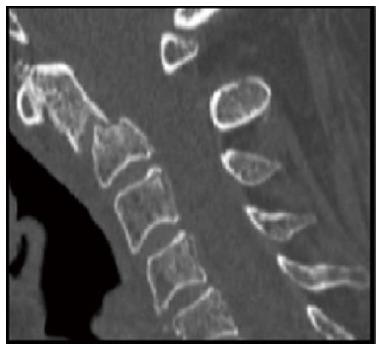

Odontoid fractures account for 5% to 15% of all cervical spine injuries and 1% to 2% of all spine fractures. Type II fractures are the most common fracture pattern in elderly patients. Treatment (rigid and non-rigid immobilization, anterior screw fixation of the odontoid and posterior C1-C2 fusion) remains controversial and represents a unique challenge for the treating surgeon. The aims of treatment in the elderly is to quickly restore pre-injury function while decreasing morbidity and mortality associated with inactivity, immobilization with rigid collar and prolonged hospitalization. Conservative treatment of type II odontoid fractures is associated with relatively high rates of non-union and in a few cases delayed instability. Options for treatment of symptomatic non-unions include surgical fixation or prolonged rigid immobilization. In this report we present the case of a 73-year-old woman with post-traumatic odontoid non-union successfully treated with Teriparatide systemic anabolic therapy. Complete fusion and resolution of the symptoms was achieved 12 wk after the onset of the treatment. Several animal and clinical studies have confirmed the potential role of Teriparatide in enhancing fracture healing. Our case suggests that Teriparatide may have a role in improving fusion rates of C2 fractures in elderly patients.

齿突骨折占所有颈椎损伤的5%至15%,占所有脊柱骨折的1%至2%。Ⅱ型骨折是老年患者中最常见的骨折类型。治疗方法(刚性和非刚性固定、齿突前路螺钉固定和C1-C2后路融合)仍存在争议,对治疗外科医生来说是一项独特的挑战。老年患者的治疗目标是在降低因活动减少、使用刚性颈托固定和长期住院相关的发病率和死亡率的同时,迅速恢复伤前功能。Ⅱ型齿突骨折的保守治疗与相对较高的不愈合率相关,在少数情况下会出现延迟性不稳定。有症状的不愈合的治疗选择包括手术固定或长期刚性固定。在本报告中,我们介绍了一例73岁女性创伤后齿突不愈合患者,通过特立帕肽全身合成代谢疗法成功治疗的病例。治疗开始12周后实现了完全融合并症状消失。多项动物和临床研究证实了特立帕肽在促进骨折愈合方面的潜在作用。我们的病例表明,特立帕肽可能在提高老年患者C2骨折的融合率方面发挥作用。